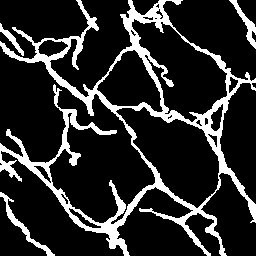

Semantic segmentation of blood vessels is an important task in medical image analysis, but its progress is often hindered by the scarcity of large annotated datasets and the poor generalization of models across different imaging modalities. A key aspect is the tendency of Convolutional Neural Networks (CNNs) to learn texture-based features, which limits their performance when applied to new domains with different visual characteristics. We hypothesize that leveraging geometric priors of vessel shapes, such as their tubular and branching nature, can lead to more robust and data-efficient models. To investigate this, we introduce VessShape, a methodology for generating large-scale 2D synthetic datasets designed to instill a shape bias in segmentation models. VessShape images contain procedurally generated tubular geometries combined with a wide variety of foreground and background textures, encouraging models to learn shape cues rather than textures. We demonstrate that a model pre-trained on VessShape images achieves strong few-shot segmentation performance on two real-world datasets from different domains, requiring only four to ten samples for fine-tuning. Furthermore, the model exhibits notable zero-shot capabilities, effectively segmenting vessels in unseen domains without any target-specific training. Our results indicate that pre-training with a strong shape bias can be an effective strategy to overcome data scarcity and improve model generalization in blood vessel segmentation.